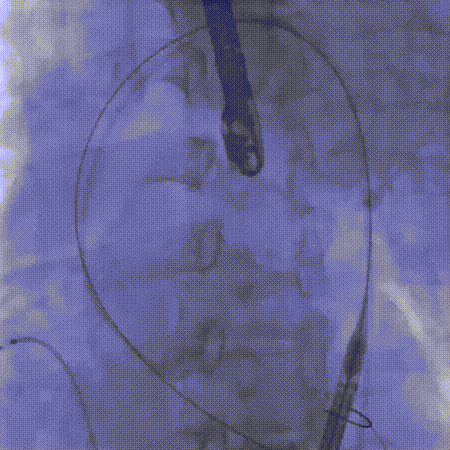

术中DSA与手术操作

经左侧入路,穿刺建立手术通道,PCI术后,主动脉根部无预扩,精准植入预装干瓣ProStyle A®AV29人工生物瓣膜;确认瓣膜植入位置理想,微量瓣周漏,主动脉瓣血动力学显著改善。

主动脉根部造影

送入输送系统

初始定位

瓣膜释放至80%近工作位观察

稳定脱钩

22球囊后扩

最终造影,形态位置良好

入路血管造影,管壁形态良好